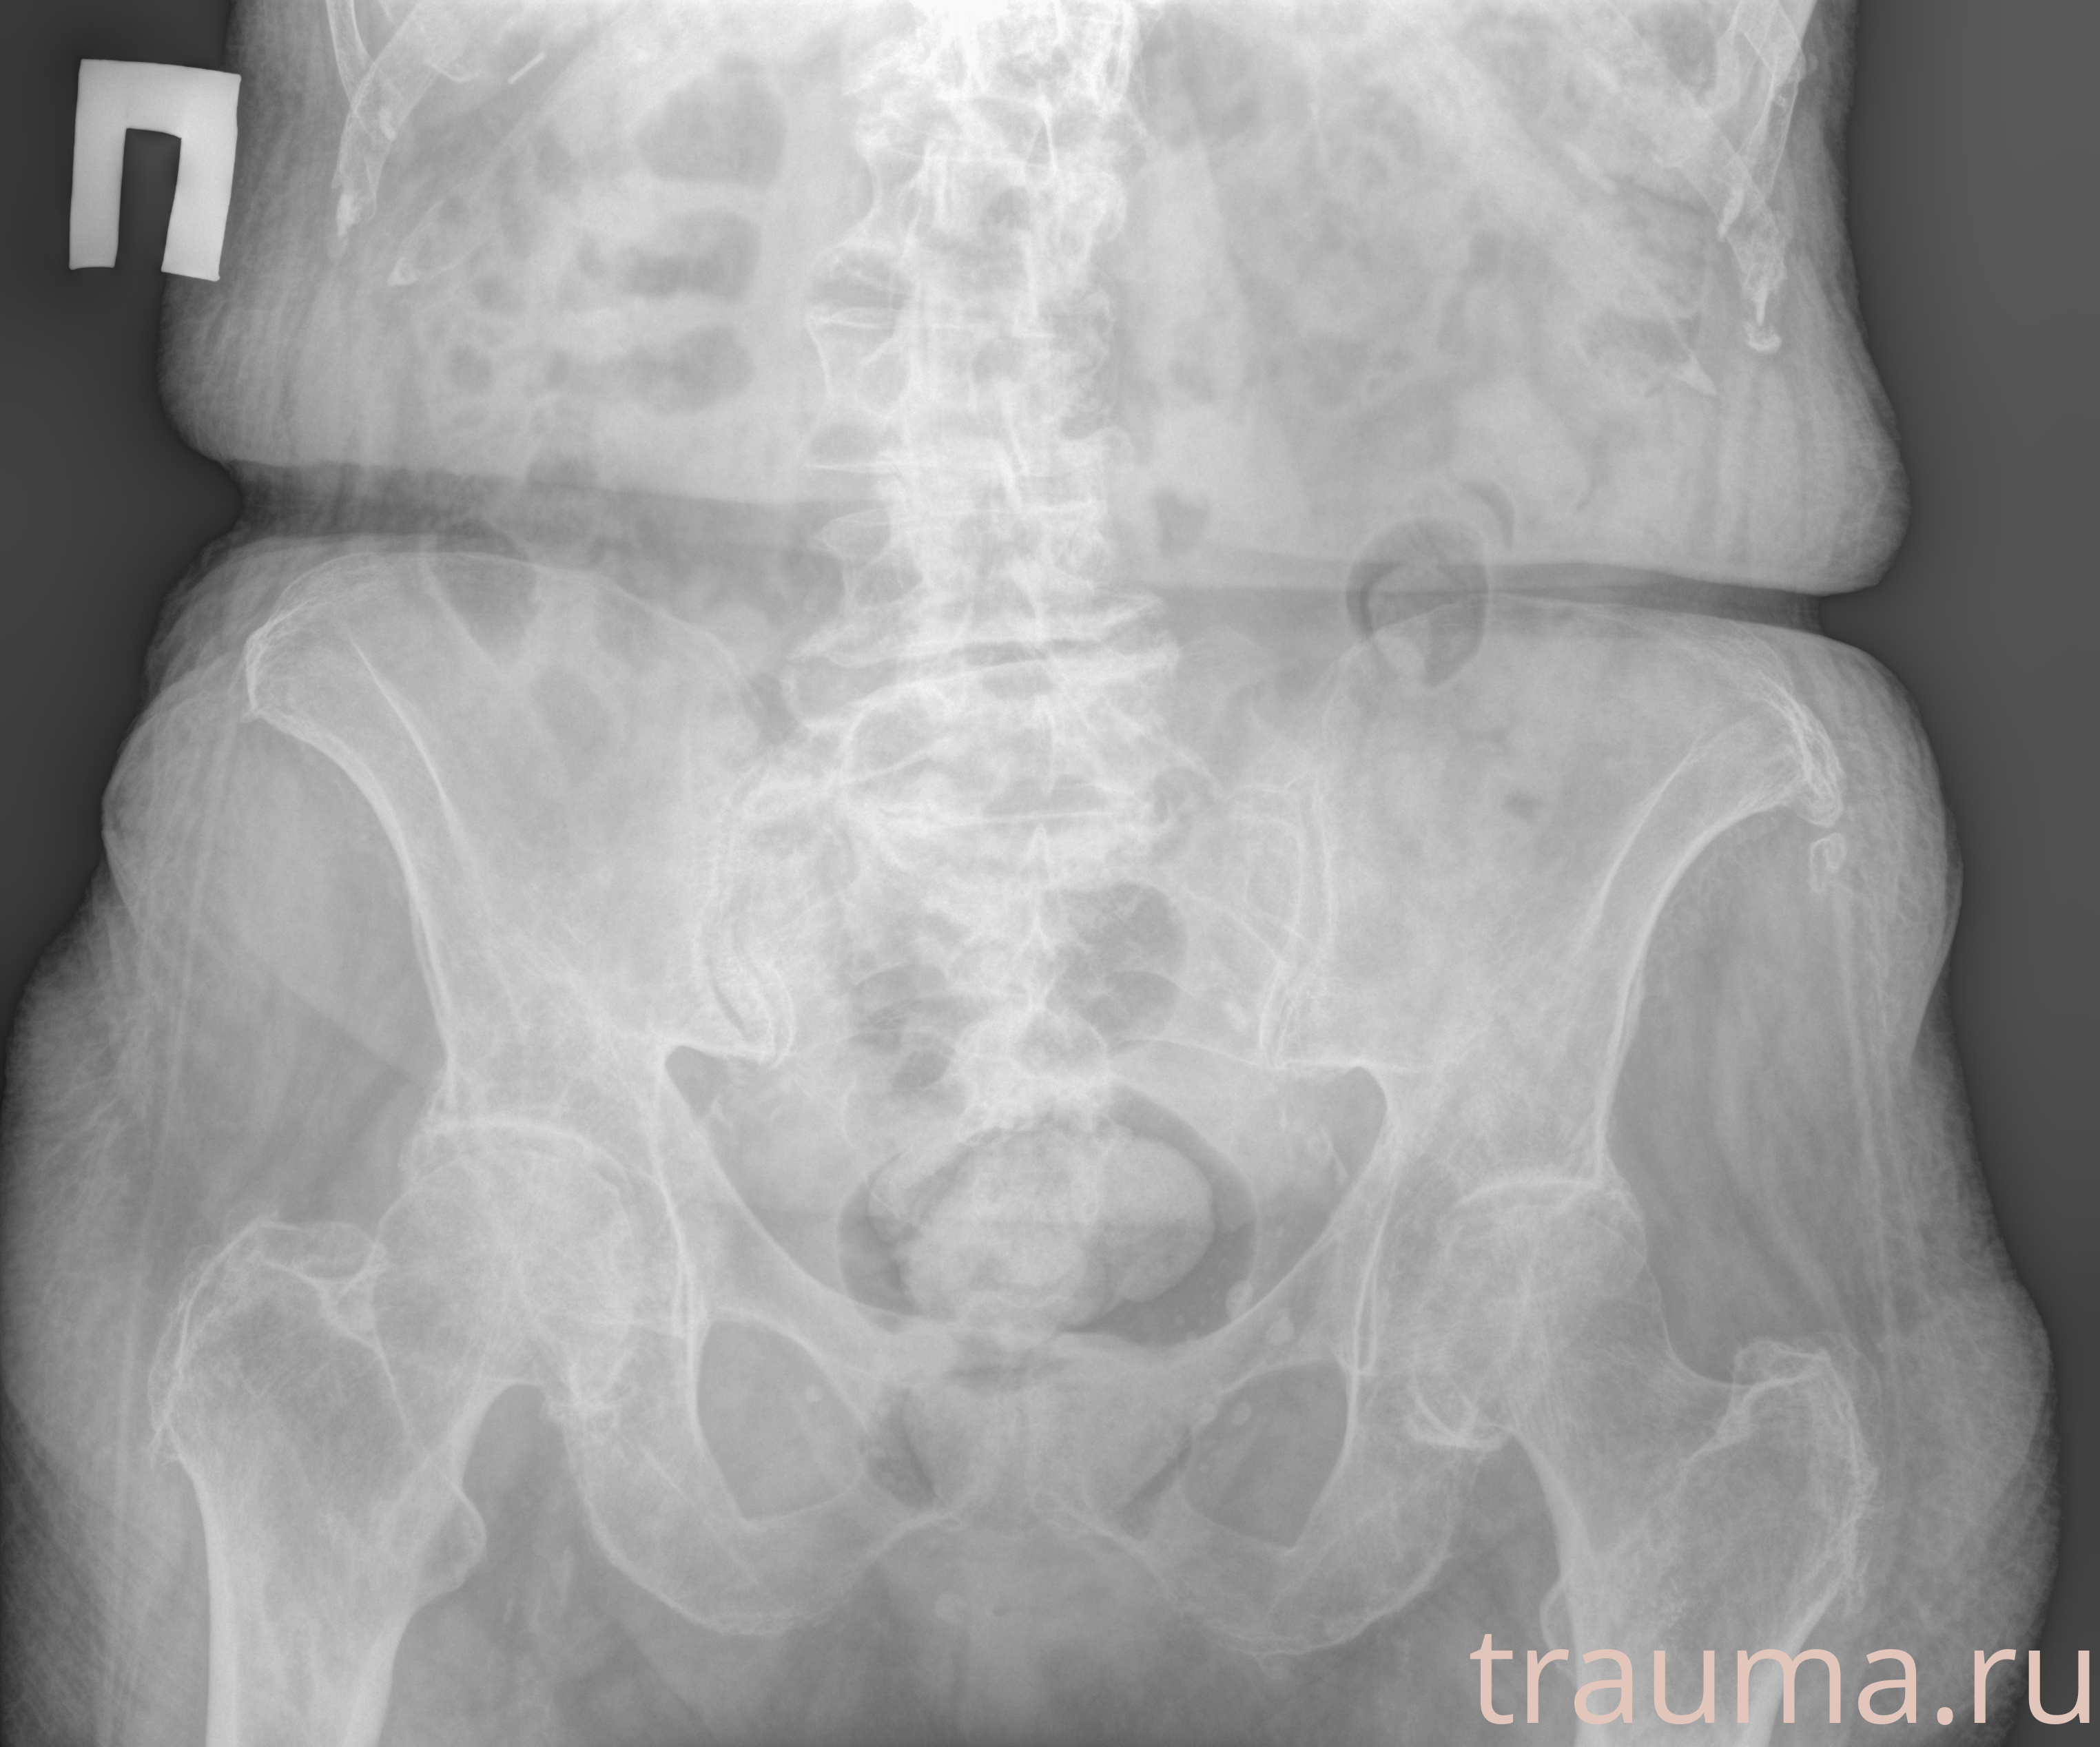

Рентгенограммы

Рентген на дому: по вашему адресу приезжает врач-рентгенолог, травматолог-ортопед с мобильным рентгеновским аппаратом, проводит диагностику травмы или заболевания, делает необходимые рентгенограммы, дает рекомендации по дальнейшему лечению. Получить качественные снимки в домашних условиях возможно благодаря уникальной методике, разработанной МосРентген Центром для института  Склифосовского

при переломе шейки бедра и пневмонии от компании МосРентген Центр - партнера Института имени Склифосовского